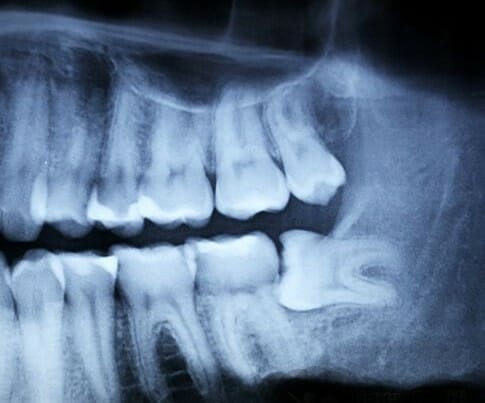

Verstandskiezen danken hun naam aan het feit dat ze doorkomen als iemand volwassen wordt. Echter

De term verstandskies wordt gebruikt voor een kies die niet kan doorbreken en weggedrukt wordt.